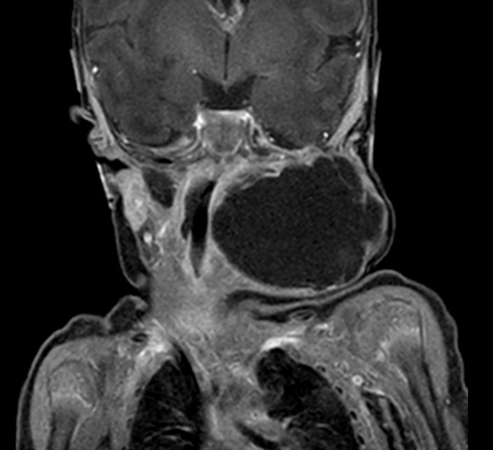

Coronal mDIXON XD - T2w TSE (Water only)

Coronal mDIXON XD - T2w TSE (In Phase)